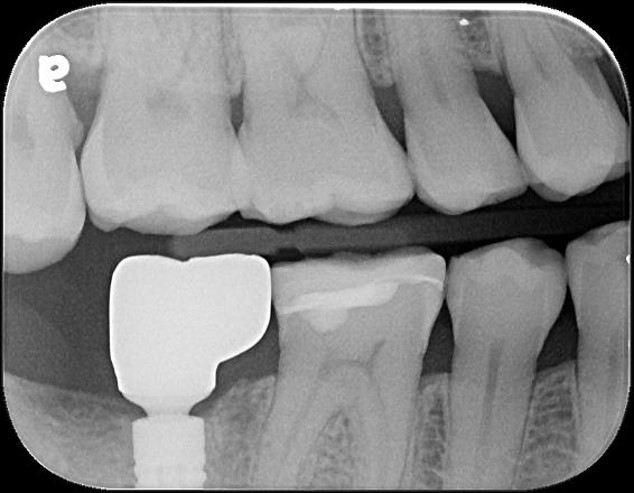

治療前,二次蛀牙,咬頭受損

蛀牙未到牙髓

當蛀牙破壞程度大